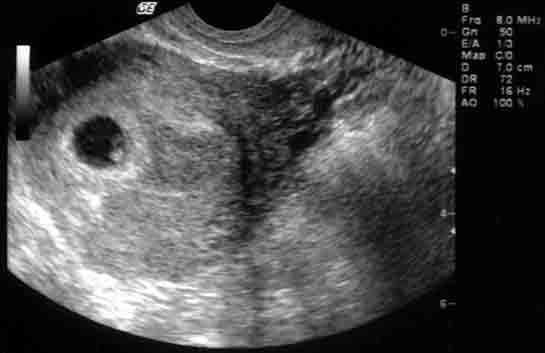

| 36 haftalık gebelik, bir hamilelik sürecinin önemli bir aşamasını temsil eder. Bu dönem, fetüsün gelişiminde kritik bir dönemdir ve anne adayının sağlığı bakımından da dikkate alınması gereken birçok faktör vardır. Bu makalede, 36 haftalık gebelik sürecinin özellikleri, anne adayı ve fetüs üzerindeki etkileri ile birlikte, bu dönemde dikkat edilmesi gereken konular ele alınacaktır. Fetüs Gelişimi 36 haftalık gebelikte fetüs, doğuma oldukça yakın bir dönemde bulunmaktadır. Bu aşamada fetüsün gelişimi ile ilgili bazı önemli noktalar şunlardır:

36 haftalık gebelik sürecinde yaşadıklarım gerçekten çok ilginç. Bebeğimin boyunun 47 cm ve ağırlığının 2 kg 700 gram olması beni heyecanlandırıyor. Her gün ortalama 30 gram alması da bu süreçteki gelişimini gösteriyor. Bebeğin doğuma hazırlandığını bilmek güzel ama bu haftayı atlatmanın verdiği rahatlıkla birlikte üzerimdeki yükün biraz hafiflemesi de sevindirici. Hormonal değişimler nedeniyle bedenimdeki gevşeme ve yumuşama beni yavaşlatıyor. Yürüyüşlerim değişti, bu da normal. Ancak bel ve pelvisteki ağrılar beni rahatsız ediyor. Yemek yeme konusunda da sıkıntılar yaşıyorum, bebeğim artık çok yer kaplıyor. Küçük porsiyonlarla beslenmek zorundayım. Mide yanmamın hafiflemesi, nefes almamı kolaylaştırdı ama bebeğim aşağı doğru inmeye çalıştıkça alt karın bölgesinde baskı hissediyorum, bu da rahatsız edici. Braxton Hicks kasılmalarının daha fazla hissedilmesi de dikkatimi çekiyor. Doğum sancılarının başlaması için her an hazırlıklı olmam gerektiğini biliyorum. Bebeğimin hareketlerinde azalma olursa ya da vajinal kanama yaşarsam hemen doktora gitmem gerektiğini unutmayacağım. Vajinal akıntıdaki artış beni endişelendiriyor ama cinsel birliktelikten sonra lekelenmenin normal olduğunu öğrenmek biraz olsun rahatlatıyor. Karın kaşıntım da dayanılmaz hale geldi; badem yağı ve E vitamini kremleri kullanmaya başladım. Uyku sorunlarıyla başa çıkmak için rahat kıyafetler giymek zorundayım. Ayaklarımda ve bileklerimdeki şişlik beni oldukça rahatsız ediyor fakat bol sıvı tüketmeye dikkat ediyorum. Halsizlik hissi normal ama doğumun yaklaşmasıyla birlikte bir enerji patlaması yaşıyorum. Artık tuvalet ihtiyacım da arttı, bu durum da yeni bir alışkanlık haline geldi. Tüm bu süreç gerçekten hem zorlu hem de heyecan verici!